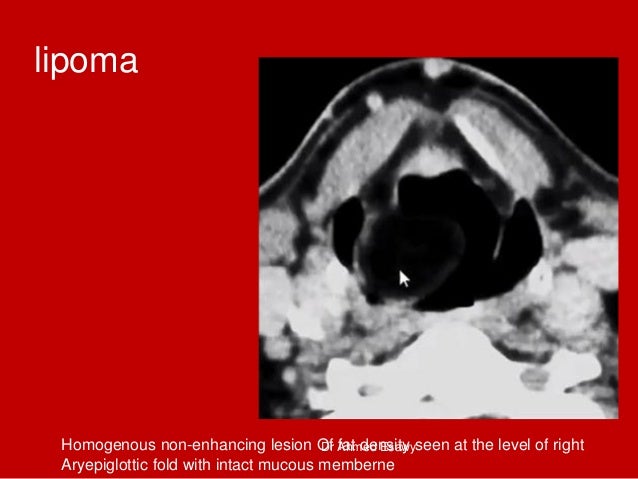

72. 72. lipoma Homogenous non-enhancing lesion Of fat density seen at the level of right Aryepiglottic fold with intact mucous memberne Dr Ahmed Esawy

92. 92. Lipoma right aryepiglottic fold • Axial contrast-enhanced CT scan obtained at the supraglottic level shows a homogeneous, nonenhancing lesion isoattenuating to fat at the level of the right aryepiglottic fold (arrowhead).